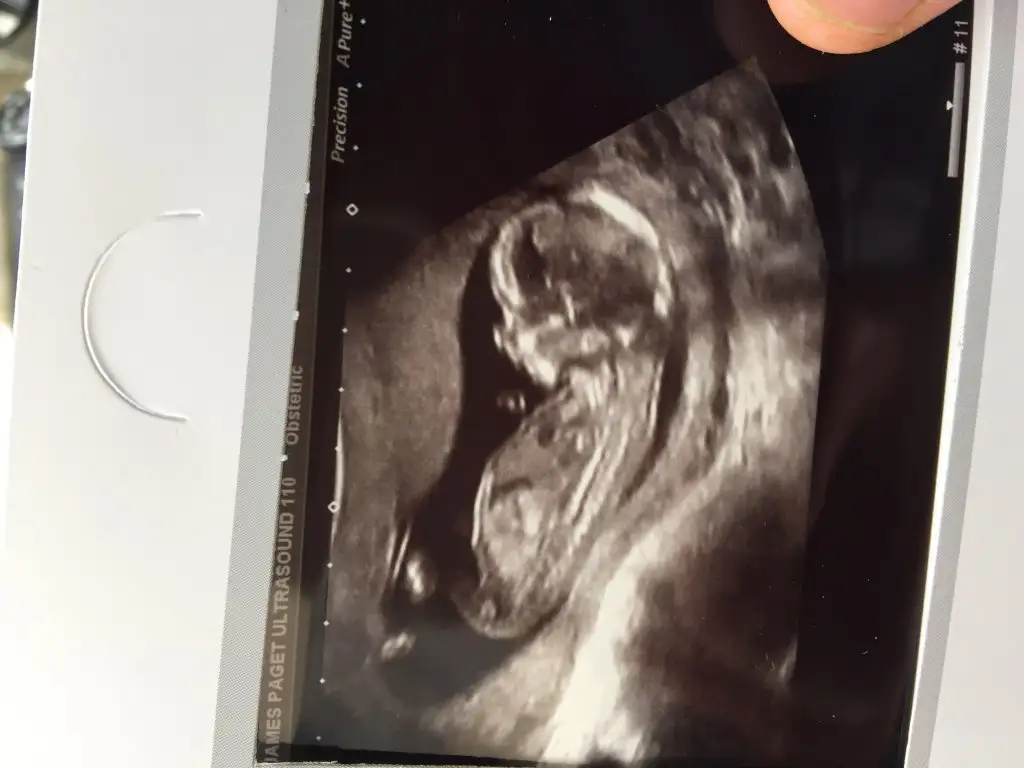

kızlar cinsiyet tahmini yapabilen var mı :)

• tp10.webp

tp10.webp

11,6 KB · Görüntüleme: 119

• tp7.webp

tp7.webp

10,6 KB · Görüntüleme: 122